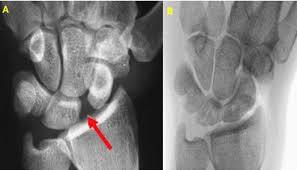

what is the pathology ?

scaphoid-lunate ligament tear